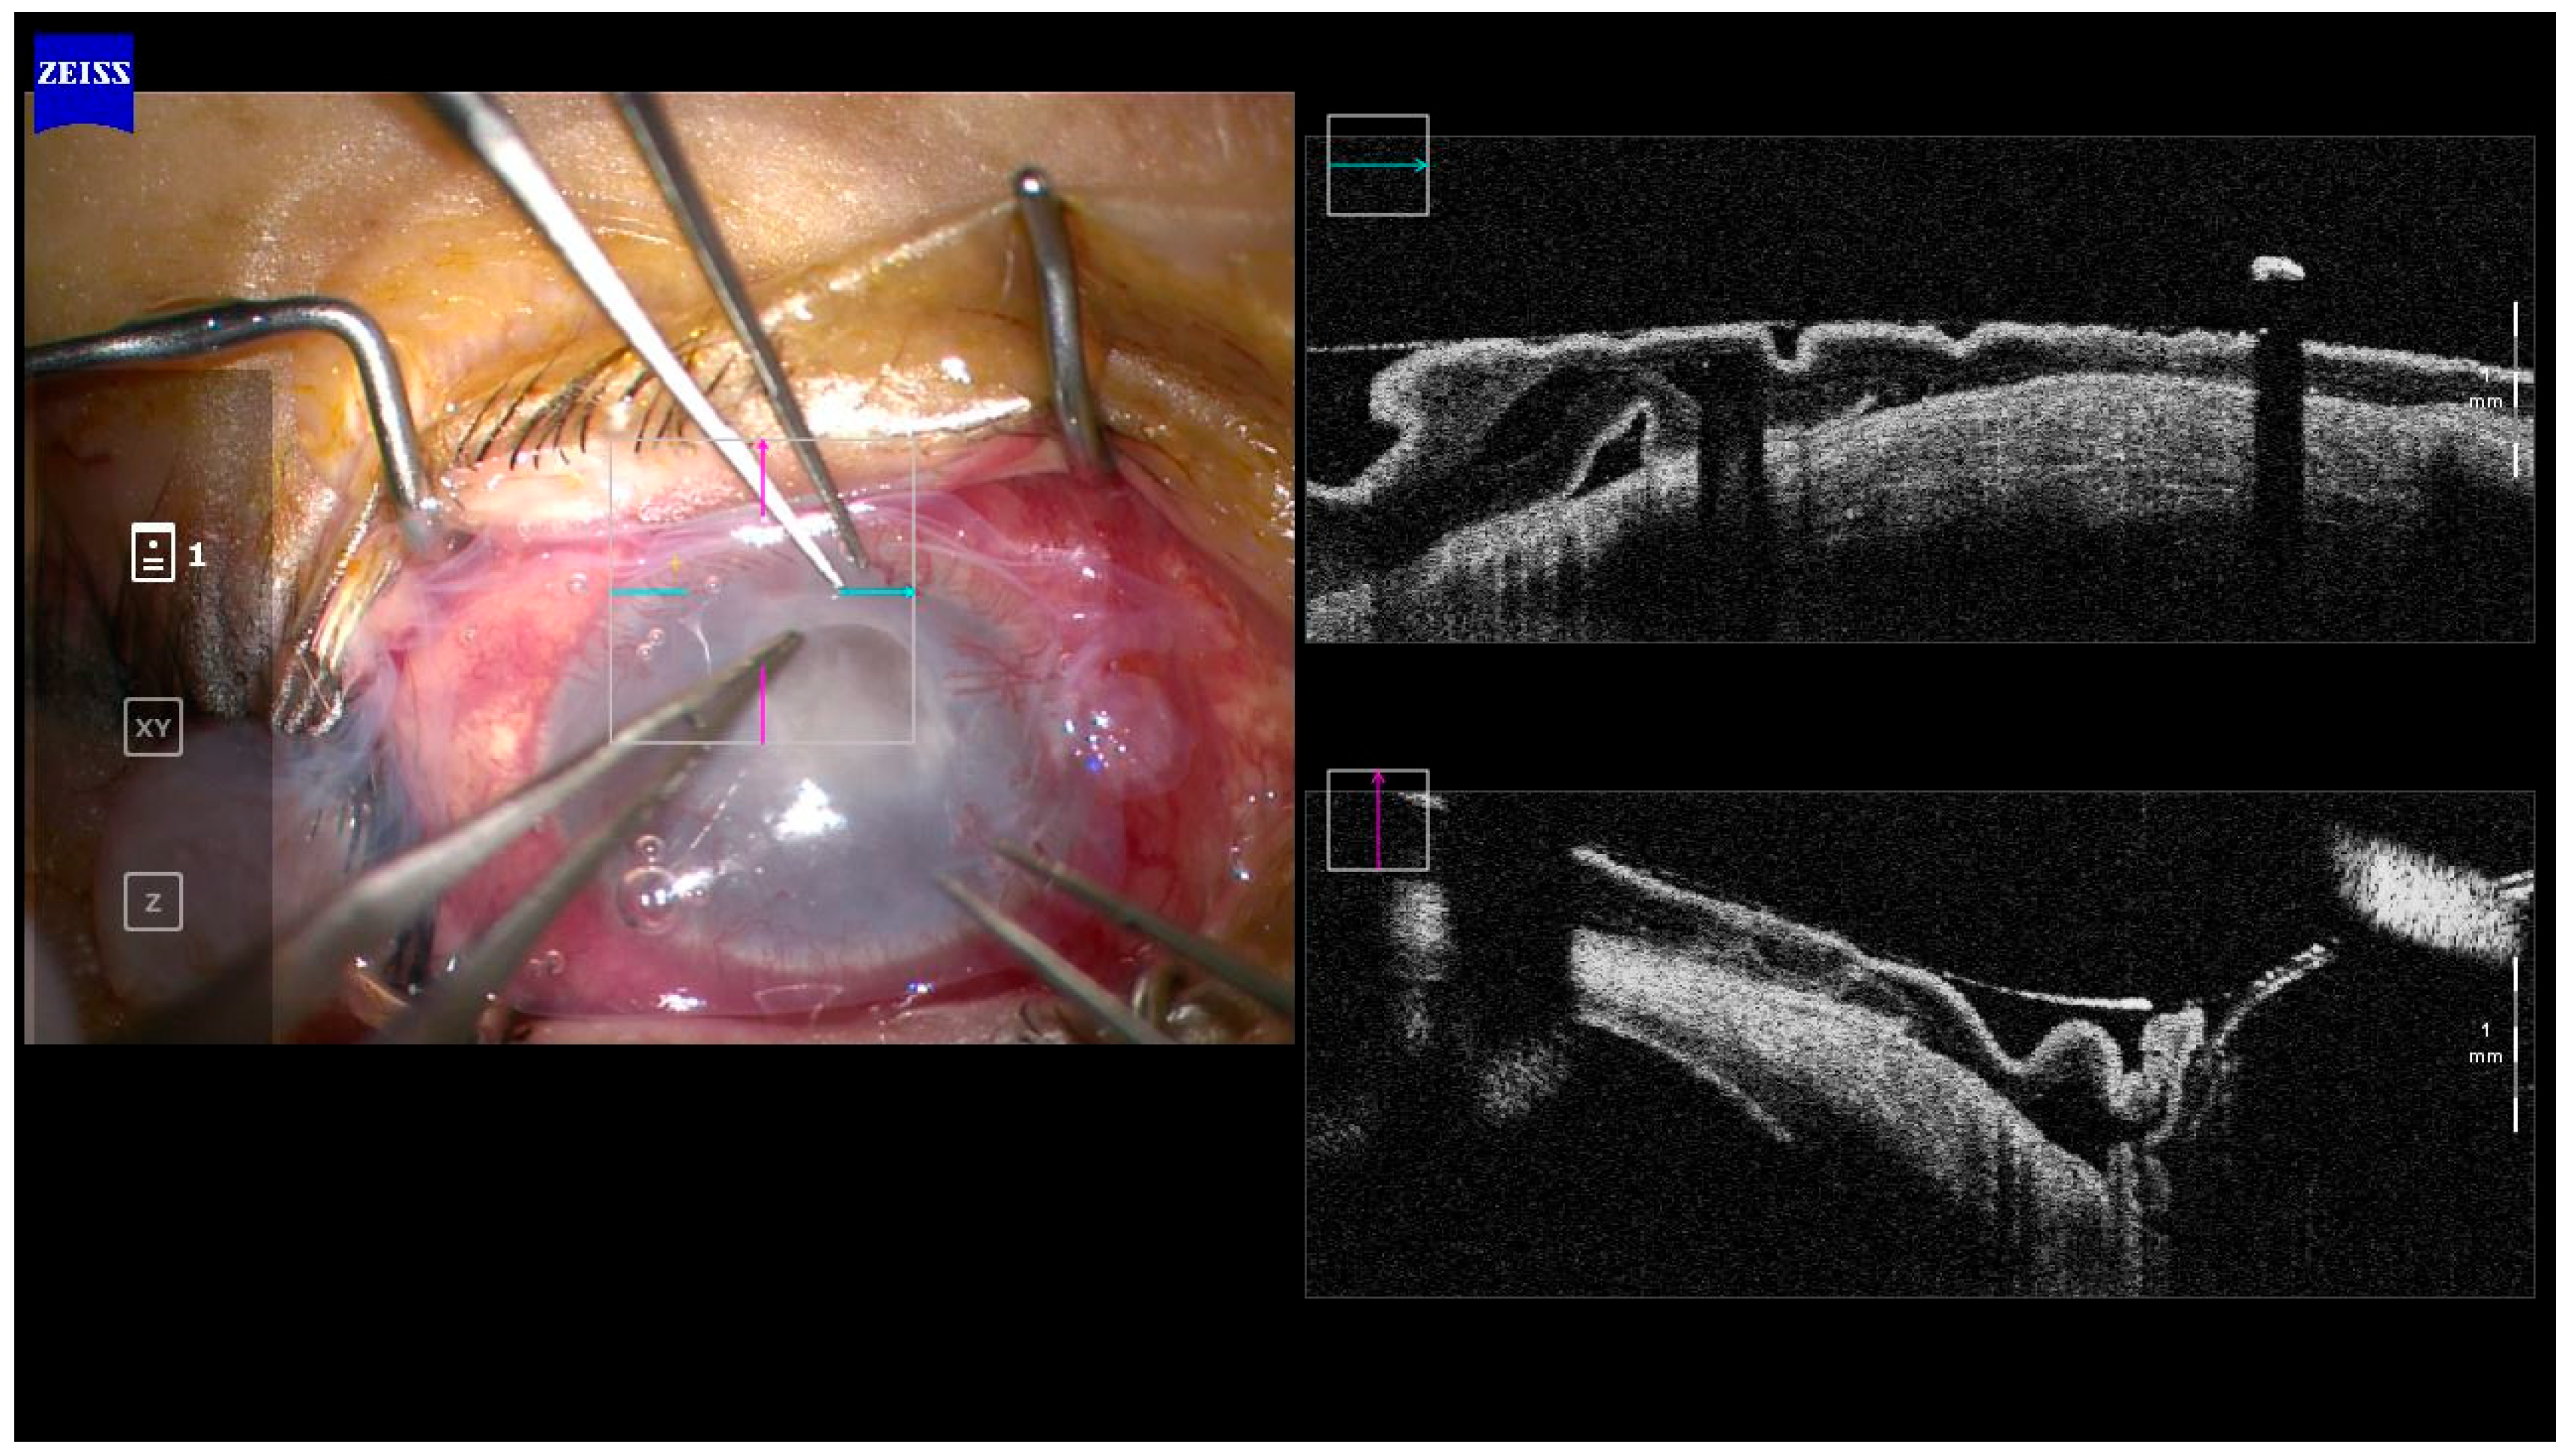

- Soliman, W.; Fathalla, A.M.; El-Sebaity, D.M.; Al-Hussaini, A.K. Spectral domain anterior segment optical coherence tomography in microbial keratitis. Graefe’s Arch. Clin. Exp. Ophthalmol. 2013, 251, 549–553. [Google Scholar] [CrossRef]

- Yamazaki, N.; Kobayashi, A.; Yokogawa, H.; Ishibashi, Y.; Oikawa, Y.; Tokoro, M.; Sugiyama, K. In vivo imaging of radial keratoneuritis in patients with acanthamoeba keratitis by anterior-segment optical coherence tomography. Ophthalmology 2014, 121, 2153–2158. [Google Scholar] [CrossRef]

- Oliveira, M.A.; Rosa, A.; Soares, M.; Gil, J.; Costa, E.; Quadrado, M.J.; Murta, J. Anterior segment optical coherence tomography in the early management of microbial keratitis: A cross-sectional study. Acta Med. Port. 2020, 33, 318–325. [Google Scholar] [CrossRef]